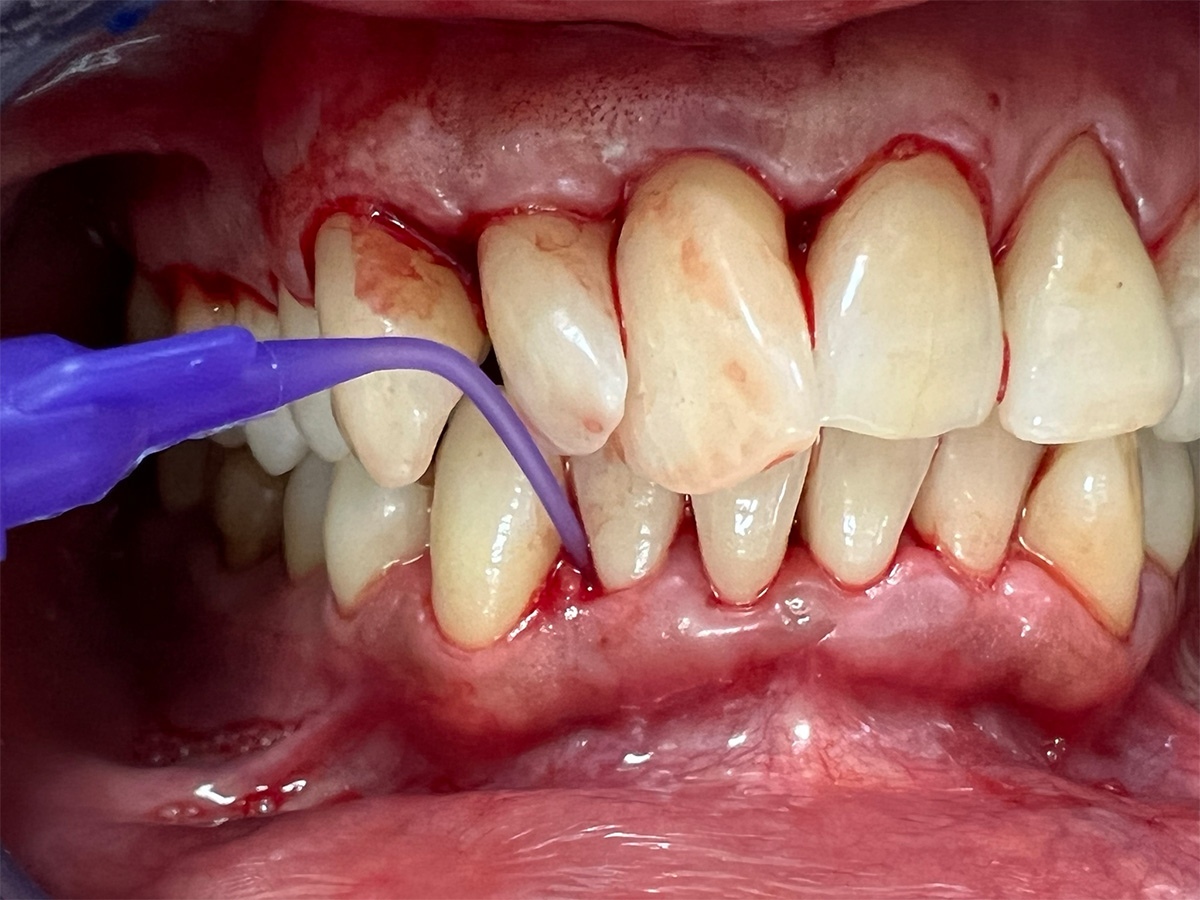

KURSINHALT

In diesem Workshop erhalten Sie umfassendes Wissen für die Behandlung von Parodontitis-Patientenen. Zunächst führt Sie Yvonne Gebhardt durch moderne subgingivale Behandlungskonzepte – das Herzstück der PA-Therapie. Anschließend erklärt Ihnen Sonja Steinert die faszinierenden Zusammenhänge des Knochenstoffwechsels: Wie Entzündungen den Knochenabbau fördern und wie Sie mit gezielter Therapie und Vitamin D gegensteuern können.

• Parodontale Krankheitsbilder erkennen